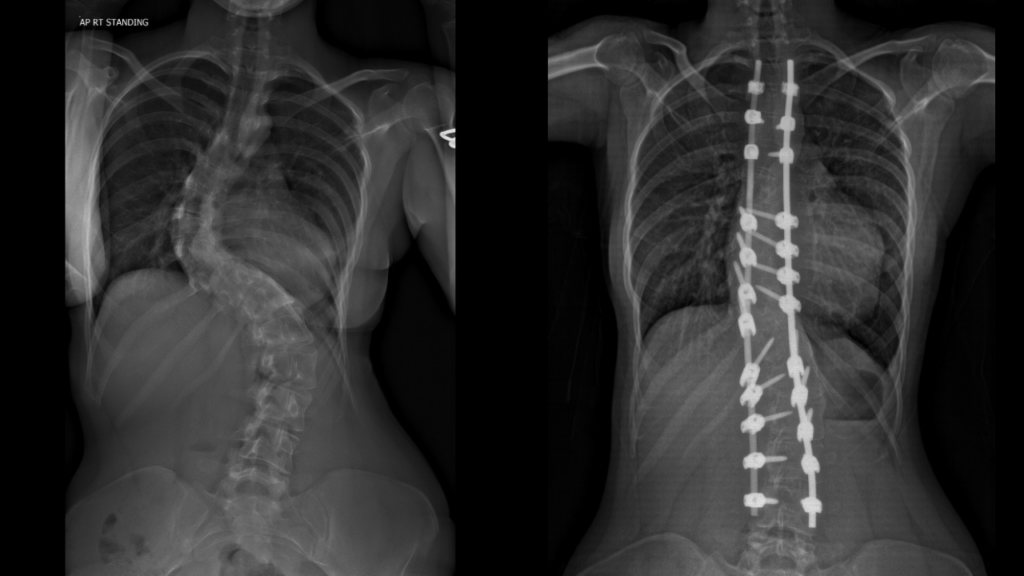

Diagnosed with scoliosis as a baby, Daisy-Mai has lived with the condition for most of her life. Scoliosis is a condition in which the spine twists and curves to the side and, in some cases, can affect posture, breathing, and overall mobility. There are about three or four children per 1000 in the UK diagnosed with scoliosis.

She underwent a nine-hour operation known as a posterior spinal fusion with costoplasty. This complex procedure involves straightening and stabilising the spine using rods and screws, which fuse sections of the spine together. As part of Daisy-Mai’s surgery, two ribs were also removed to help correct the shape of her chest and improve overall alignment.

Daisy-Mai’s spine has been fully realigned since her procedure. She is three inches taller, and her mum Louisa has described her recovery as ‘life-changing’.